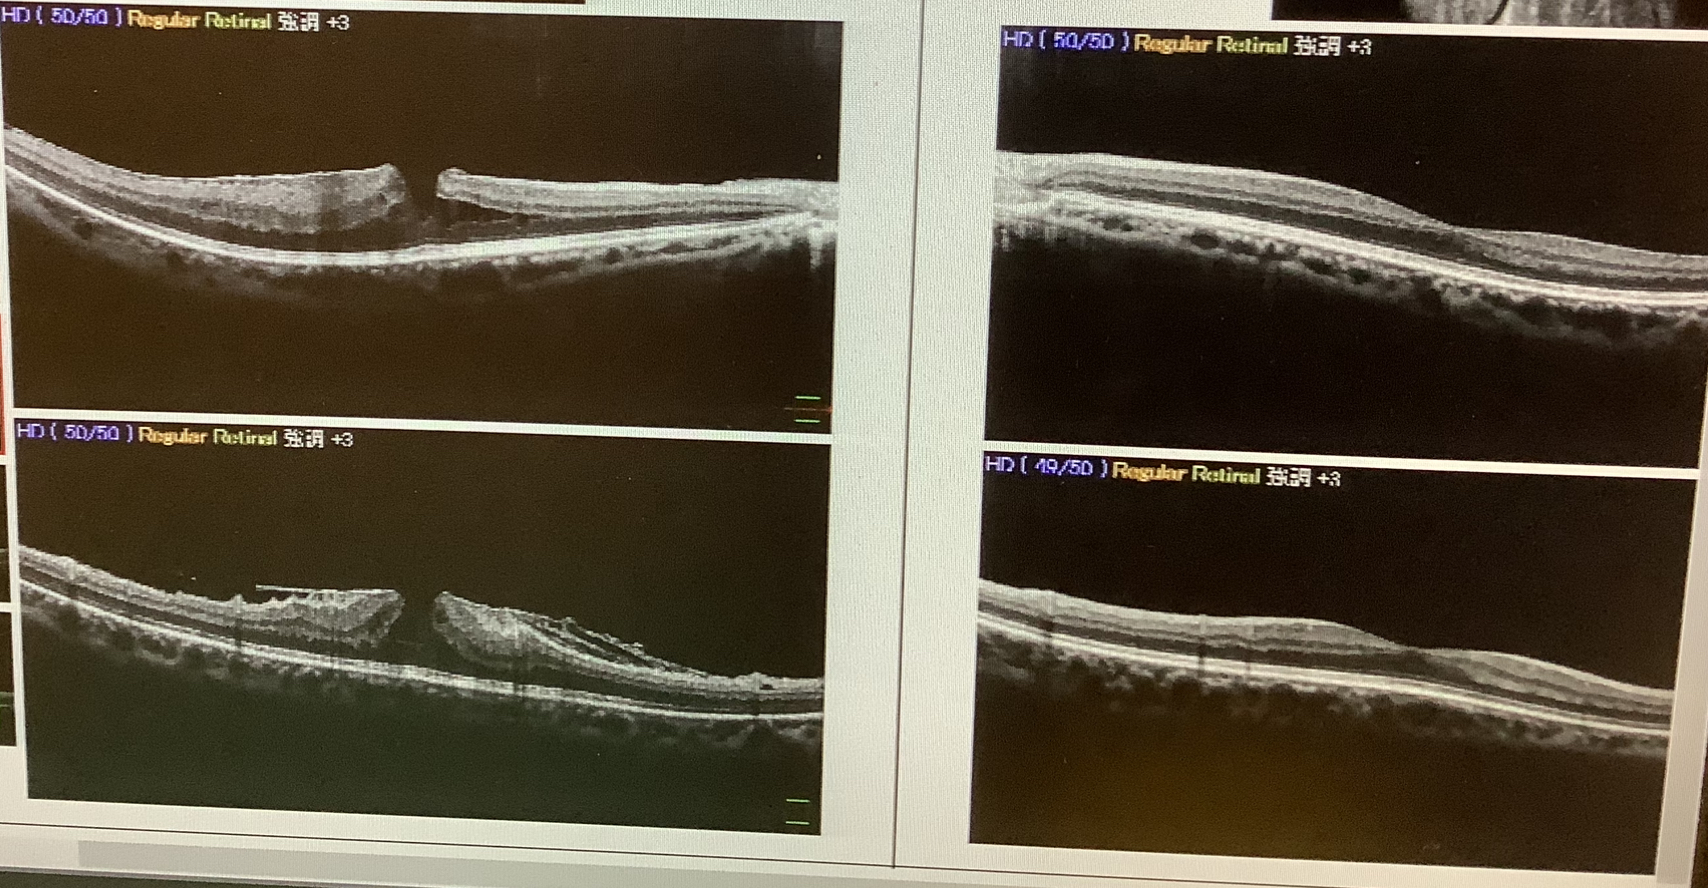

今日は73歳の女性の黄斑円孔の患者さんの手術を緊急でやらせていただきました。この方は、先週の土曜日に『2週間前くらいから左眼が見えにくい』と受診され、黄斑部が穴になっており、視力は0.5でした。元々、右眼も黄斑円孔で手術を受けた既往があり、ご本人もまた同じような病気かと思い受診されたそうですが、網膜特に黄斑の病気では早めの手術が大切なことが多いかと思います。

黄斑円孔では、黄斑部に穴ができてしまうことで、黄斑の細胞が悪くなってしまい、見えにくさを来たしてしまいますが、穴を塞げば元に戻るというものではなく、時間が経ってしまうと黄斑の細胞が変性してしまい(弱くなってしまい)、穴が塞がっても視力の回復が望めなくなってしまいます。そのため、黄斑円孔の手術はなるべく早い方がよいとされ、発症後2週間程度で手術を行うことが望ましいかと思います。もちろん、患者さん側にもクリニック側にも事情があり、2週間を過ぎてしまうこともあるかとは思いますが、なるべくは早めに手術を受けることが大事かと思います。